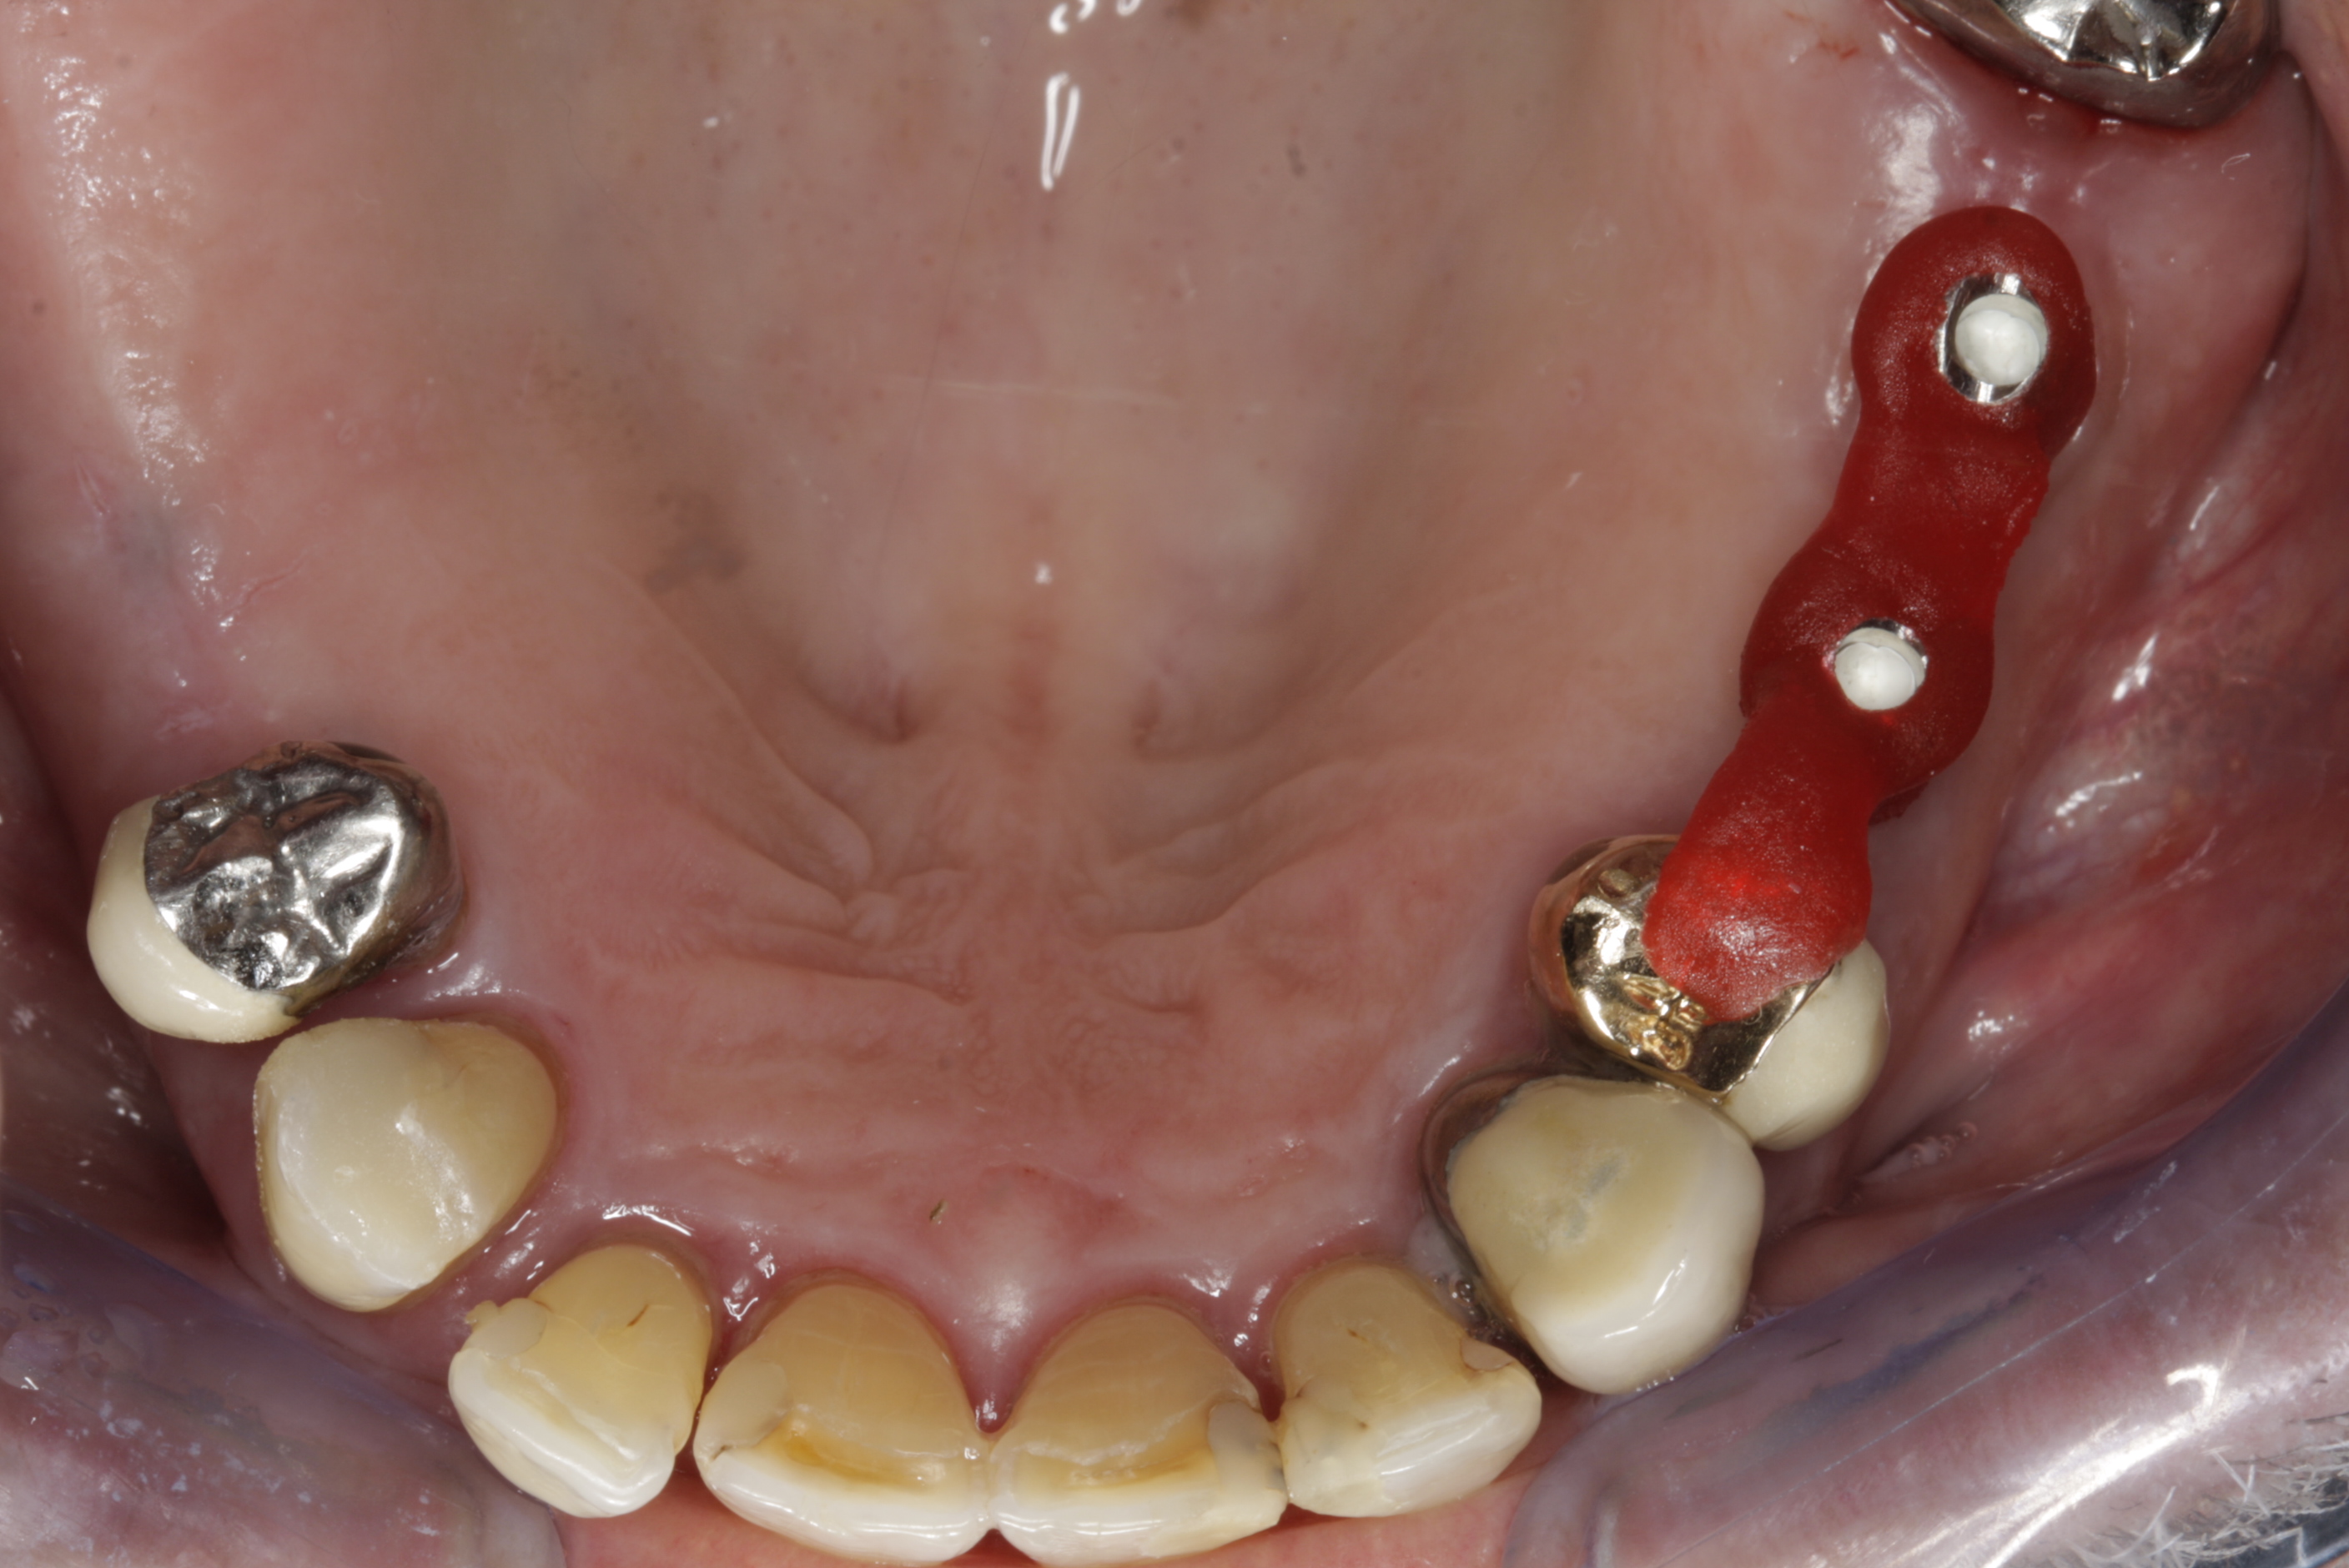

V případě chybění většího počtu zubů v postranních úsecích čelistí je možné ošetření pomocí implantátů, které nahradí ošetření pomocí snímacích náhrad kotvených na zbývajících zubech nebo patře.

Podmínkou je opět dostatečné množství kosti.

Protetické řešení může být pomocí můstku, který je kotvený na implantátech nebo pomocí jednotlivých korunek na implantátech.

V zásadě je možné do těchto můstků zařadit i přirozené zuby, zejména pokud je potřeba tyto zuby ošetřit proteticky – korunkami. Korunky nebo můstky mohou být na implantáty nacementovány nebo přišroubovány.

Zdravé zuby zůstanou zachovány a přitom náhrady jsou pevné, jako na vlastních zubech